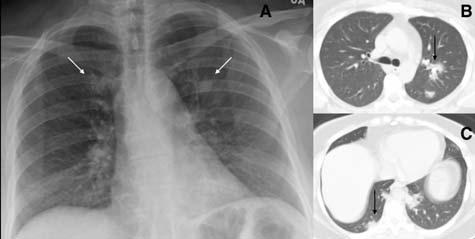

On CXR, GGO appears as an area of hazy increased

lung opacity within which margins of pulmonary vessels may be difficult to see14. These are much better seen on Computed Tomography (CT) and are less opaque compared to consolidation (Fig 1). When associated with reticular opacities, the detection becomes easier. Hazy opacities on CXR can also be diffuse making its identification challenging10 (Fig 2). In patients with proven COVID-19, GGO was seen in 20-33% of patients at presentation1113,15. Normal lung parenchyma may mimic areas of GGO in poorly taken films and/or due to overlying soft tissues such as prominent breast tissue13

Fig 1 — CXR (A) and CT (B) images of a 45-year-old male who presented with fever and cough. He had hypoxia and leukopenia on examination and his nasal swab was positive for SARS COV-2. CXR shows bilateral blurred opacities with unclear vascular margins (white arrow) with corresponding ground glass changes in the CT (black arrows). Images reproduced with permission from Covid-19 Database of the SocietaItaliana di Radiologia Medica e Interventistica.